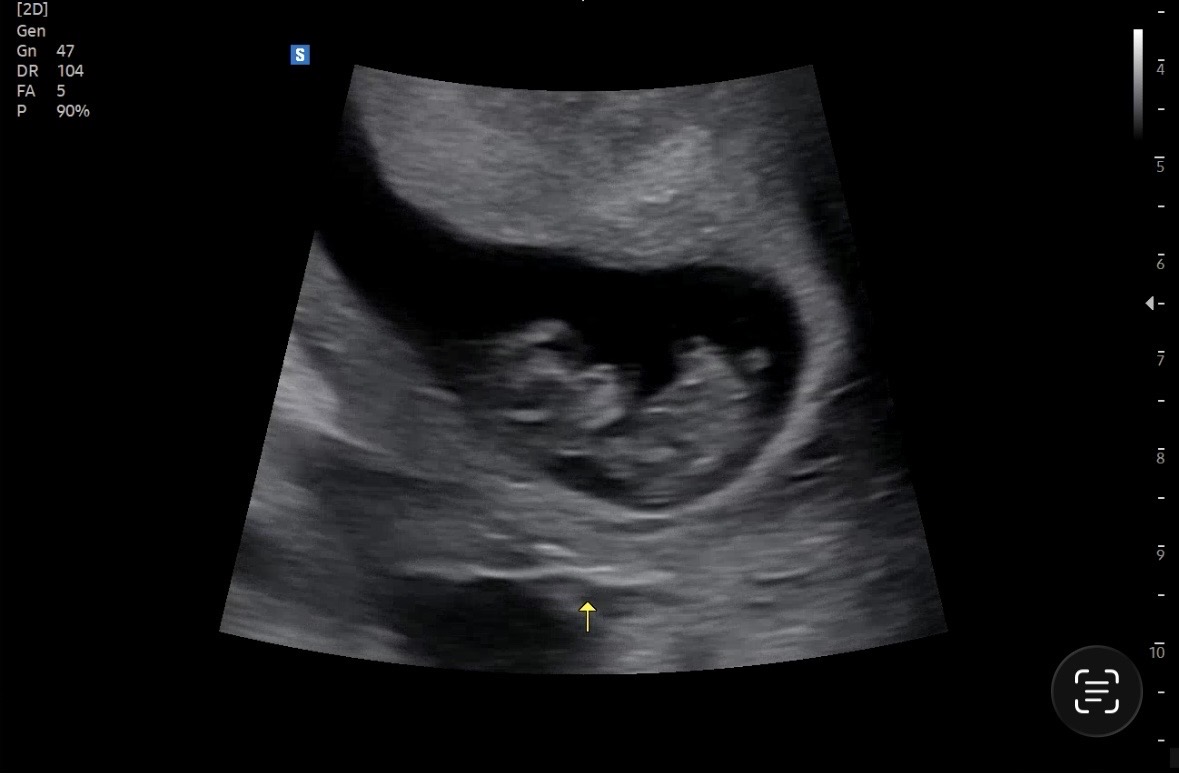

안녕하세요! 임신 10주차 맘입니다. 빌리나 인스타에서 보면 다른 엄마들의 아가 초음파가 진짜 선명하고 아가도 예뿌게 똬! 보이는데… 저희 말랑이는 매번 뿌얀느낌? 잘 안보이는 느낌이라 혹시 저 같은 분도 계시나 궁금해서 게시글 써봅니다! 혹시 나의 뱃살 탓인가…? 저처럼 초음파 뚜렷하게 안 찍히는 예비남들 계신가용??? 병원에서는 늘 아가 건강하게 잘 있다고 하시지만 괜히 불안하고 궁금한 마음에 여쭤봅니당. 감사합니다 :)